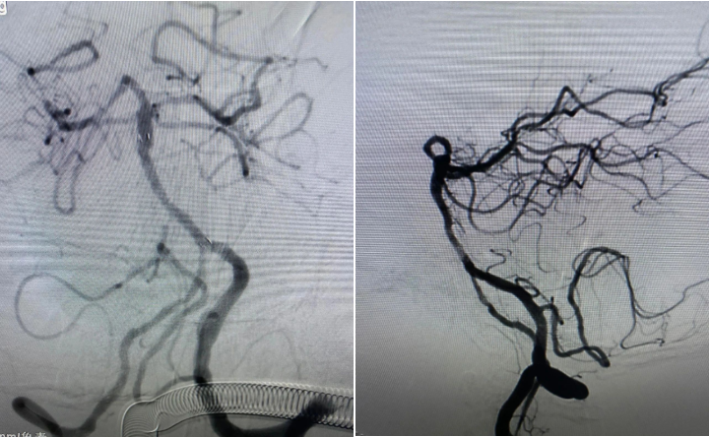

尝试回收支架至5F Navien,牵扯力量比较大,提心吊胆。

经反复收拉尝试,最终取出Enterprise 2支架。

Enterprise 2支架在血管内两端严重变形,反折的Mark恰好被Solitaire AB支架咬合取出。

Enterprise 2支架经过体外揉搓,恢复了形态,支架内一同取出的还有一大坨增生的支架内血栓。

造影未见出血,血流良好,原狭窄在第一次支架时球囊扩张,现在狭窄已缓解。狭窄远端血管内膜稍不光滑。观察30min,血流稳定,为避免再放支架血栓,同时本次预后尚未知,暂不植入第二枚支撑支架,予以替罗非班注射液应用。